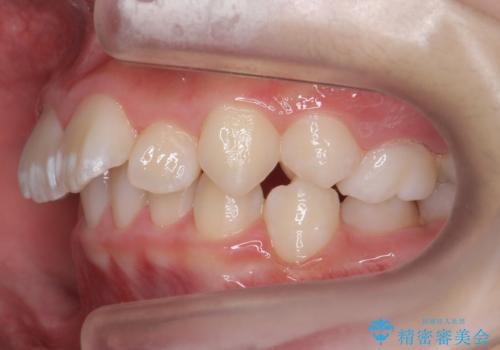

子供の出っ歯 生え代わりと成長期を利用して非抜歯で矯正

- 出っ歯を主訴に来院。

特に右側のかみ合わせがずれていたため、上の奥歯を後ろに下げています。

下顎も前方に成長し、前歯のかみ合わせも同時に深かったのを浅くすることができました。